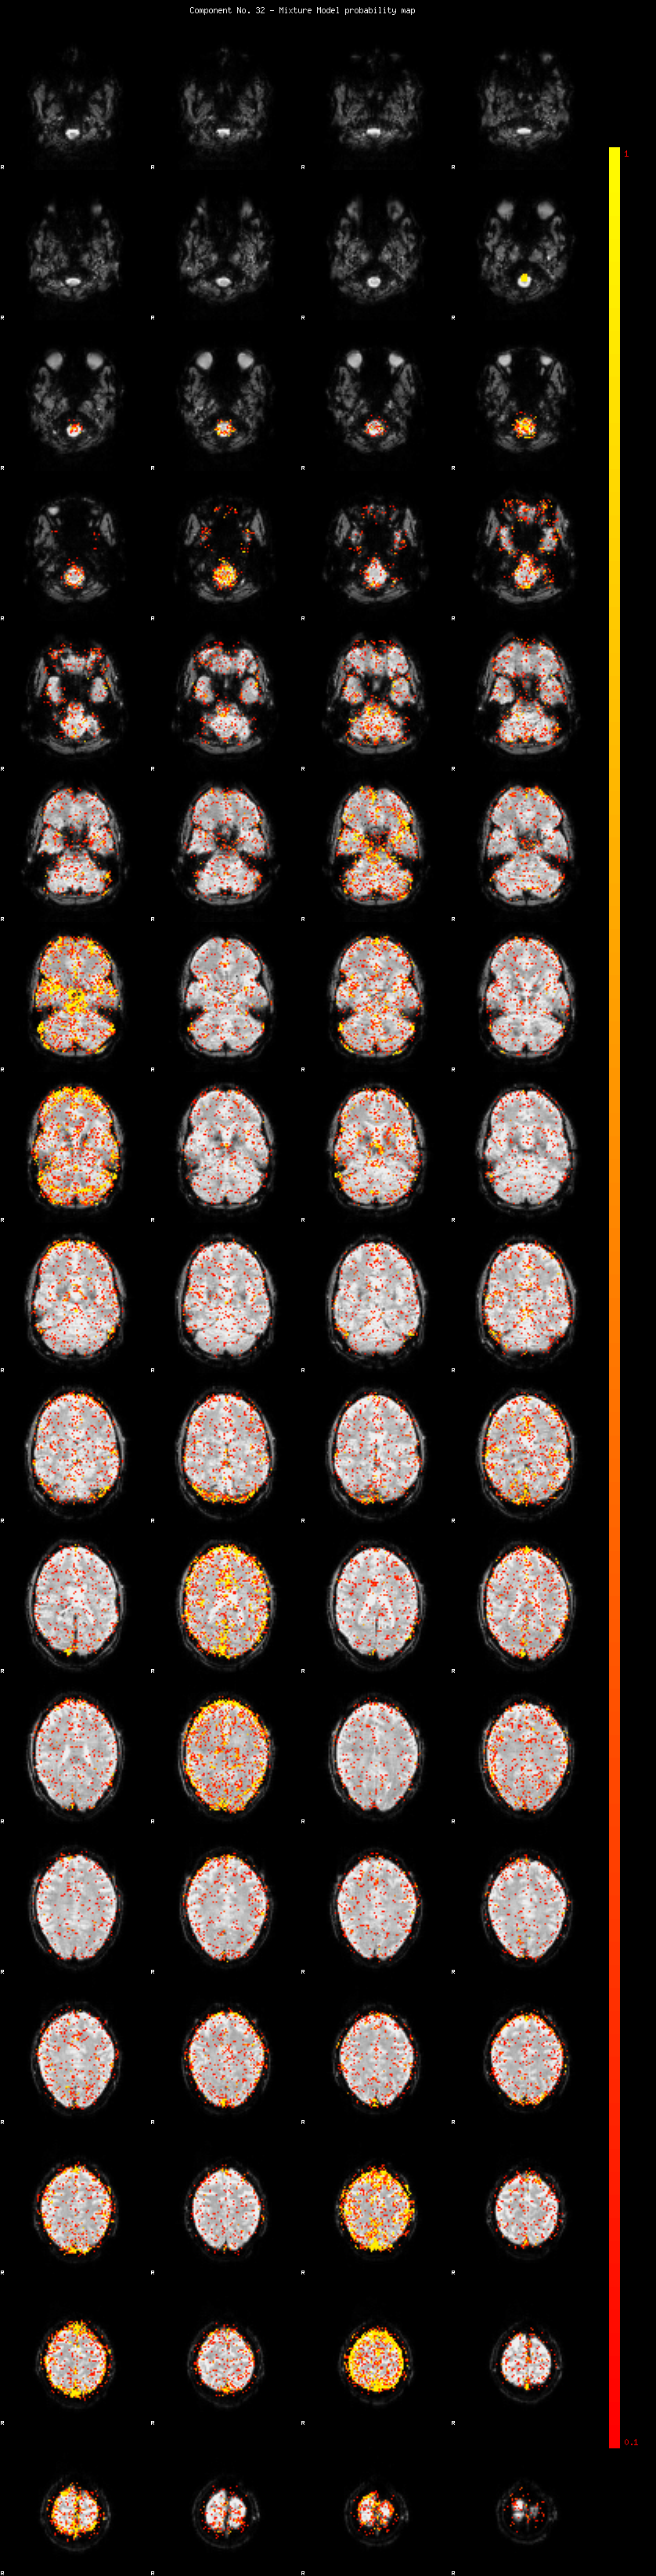

IC_32 Mixture Model fit

Means : 0.000000 3.009961 -2.574655

Vars : 1.000000 3.973511 2.309877

Prop. : 0.917670 0.040864 0.041466